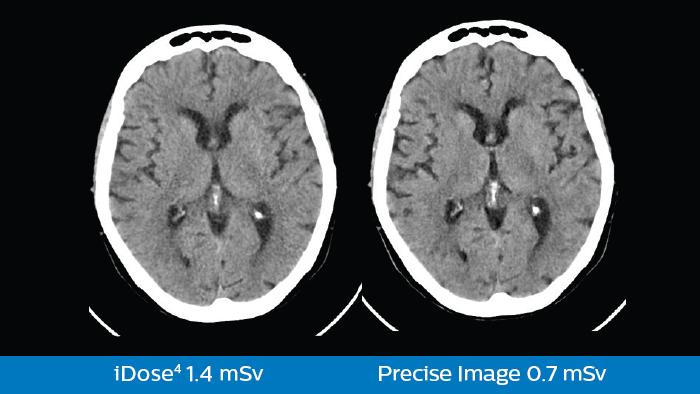

Precise Image pone el poder de una red neuronal de aprendizaje profundo a trabajar para usted para lograr reducciones dramáticas en la dosis y el ruido de la imagen. El resultado es un aumento significativo en la detectabilidad de bajo contraste aplicable a todos los protocolos y regiones, reconstruidos en menos de 60 segundos.